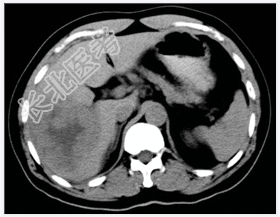

- [材料题] 患者,男性,52岁,因右上腹痛1个月、加重3天入院。体查:肝不大,肝区触痛明显,脾不大。实验室检查血AFP明显增高。行上腹部CT平扫+增强扫描。

- 简答题1、患者的诊断及依据是什么?

- 简答题2、鉴别诊断有哪些?